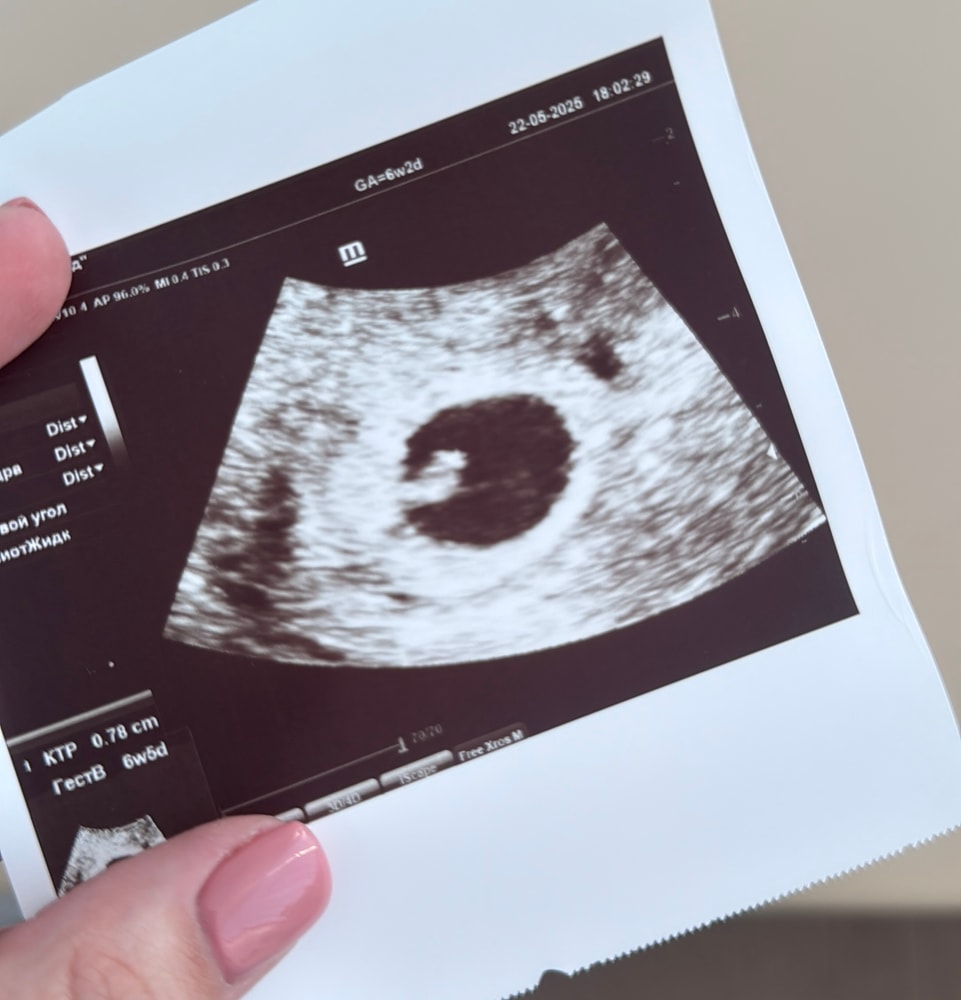

6 недель и 3 дня. Контрольное узи.

Сегодня ходила на второе узи, слушала сердце человека 🥹 Заодно нужно было проверить, как ведет себя отслойка. Все нормально, не увеличилась, 0,37*0,21 см. Но посоветовали все таки добавить утрик до 12 недели.

Плодное яйцо 1,96, эмбрион 0,8 см, желточный мешок - 5 мм, сердцебиение- 129 уд/минуту. Все соответствует сроку, а эмбрион даже чуть-чуть опережает - на 6 недель и 5 дней.